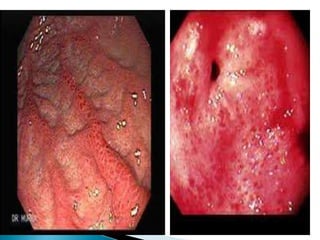

 Inflamación superficial o

profunda de la mucosa del

estomago producida por

bacterias y sustancias

irritantes (alcohol, ácido

acetilsalicílico)

 Destruyen las uniones

estrechas de las células

epiteliales y puede ocasionar

atrofia glandular.

 Se manifiesta por dolor

urente en la parte anterior e

inferior del tórax (epi-gastrio)

 Inflamación superficialo profunda de la mucosa del estomago producida por bacterias y sustancias irritantes (alcohol, ácido acetilsalicílico)  Destruyen las uniones estrechas de las células epiteliales y puede ocasionar atrofia glandular.  Se manifiesta por dolor urente en la parte anterior e inferior del tórax (epi-gastrio)